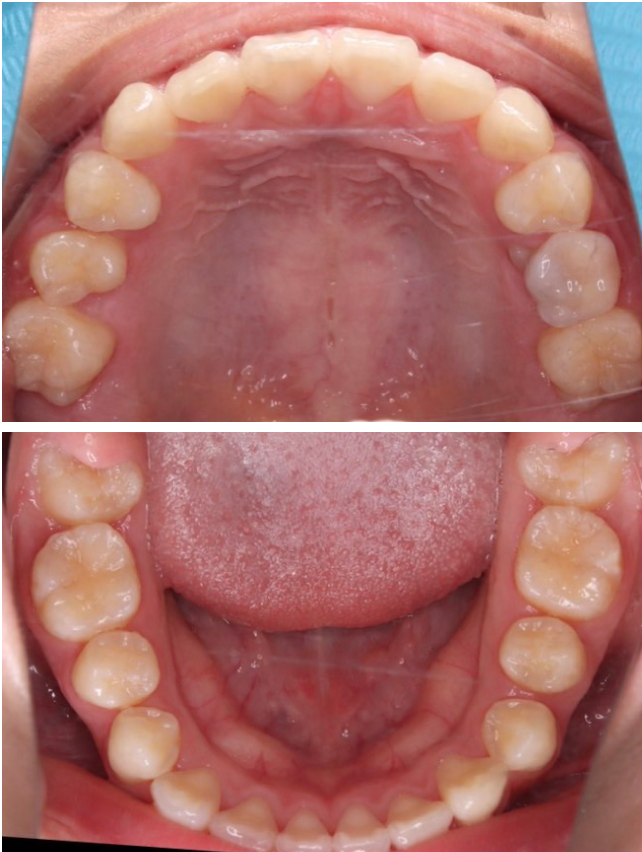

当院の症例

CASE